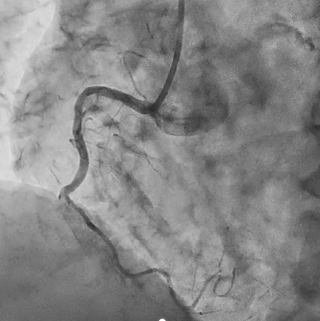

Coronary angiography revealed 100% occlusion of the right coronary artery (RCA) at segment #2, with collateral flow from the left anterior descending artery. The RCA was identified as the culprit lesion, and percutaneous coronary intervention (PCI) was planned. Engagement of the left coronary artery was achieved using a 7 Fr Launcher AL0.75 SH guiding catheter, and the lesion was crossed with a SION guidewire. A large amount of thrombus was observed in the coronary artery; therefore, thrombus aspiration followed by long balloon inflation using a 2.5 mm Ryusei balloon was performed. Although TIMI grade 1 flow remained in the #4PL branch due to residual thrombus, TIMI grade 3 flow was obtained in the #3–#4PD segments. The procedure was completed after intra-aortic balloon pump (IABP) insertion. After treatment for heart failure, coronary computed tomography performed on hospital day 21 showed thrombotic occlusion of the #4PD branch, for which a short course of direct oral anticoagulant (DOAC) therapy was initiated. Repeat coronary angiography on hospital day 33 demonstrated improved flow, although 99% stenosis persisted in the #4PL branch. As the RCA #2 lesion was identified as the culprit of acute myocardial infarction, a drug-eluting stent (Ultimaster Nagomi 3.0 ¡¿ 44 mm) was deployed in segment #2, and balloon dilation using an Agent 2.0 ¡¿ 30 mm balloon was performed for the #4PL branch, achieving successful revascularization.